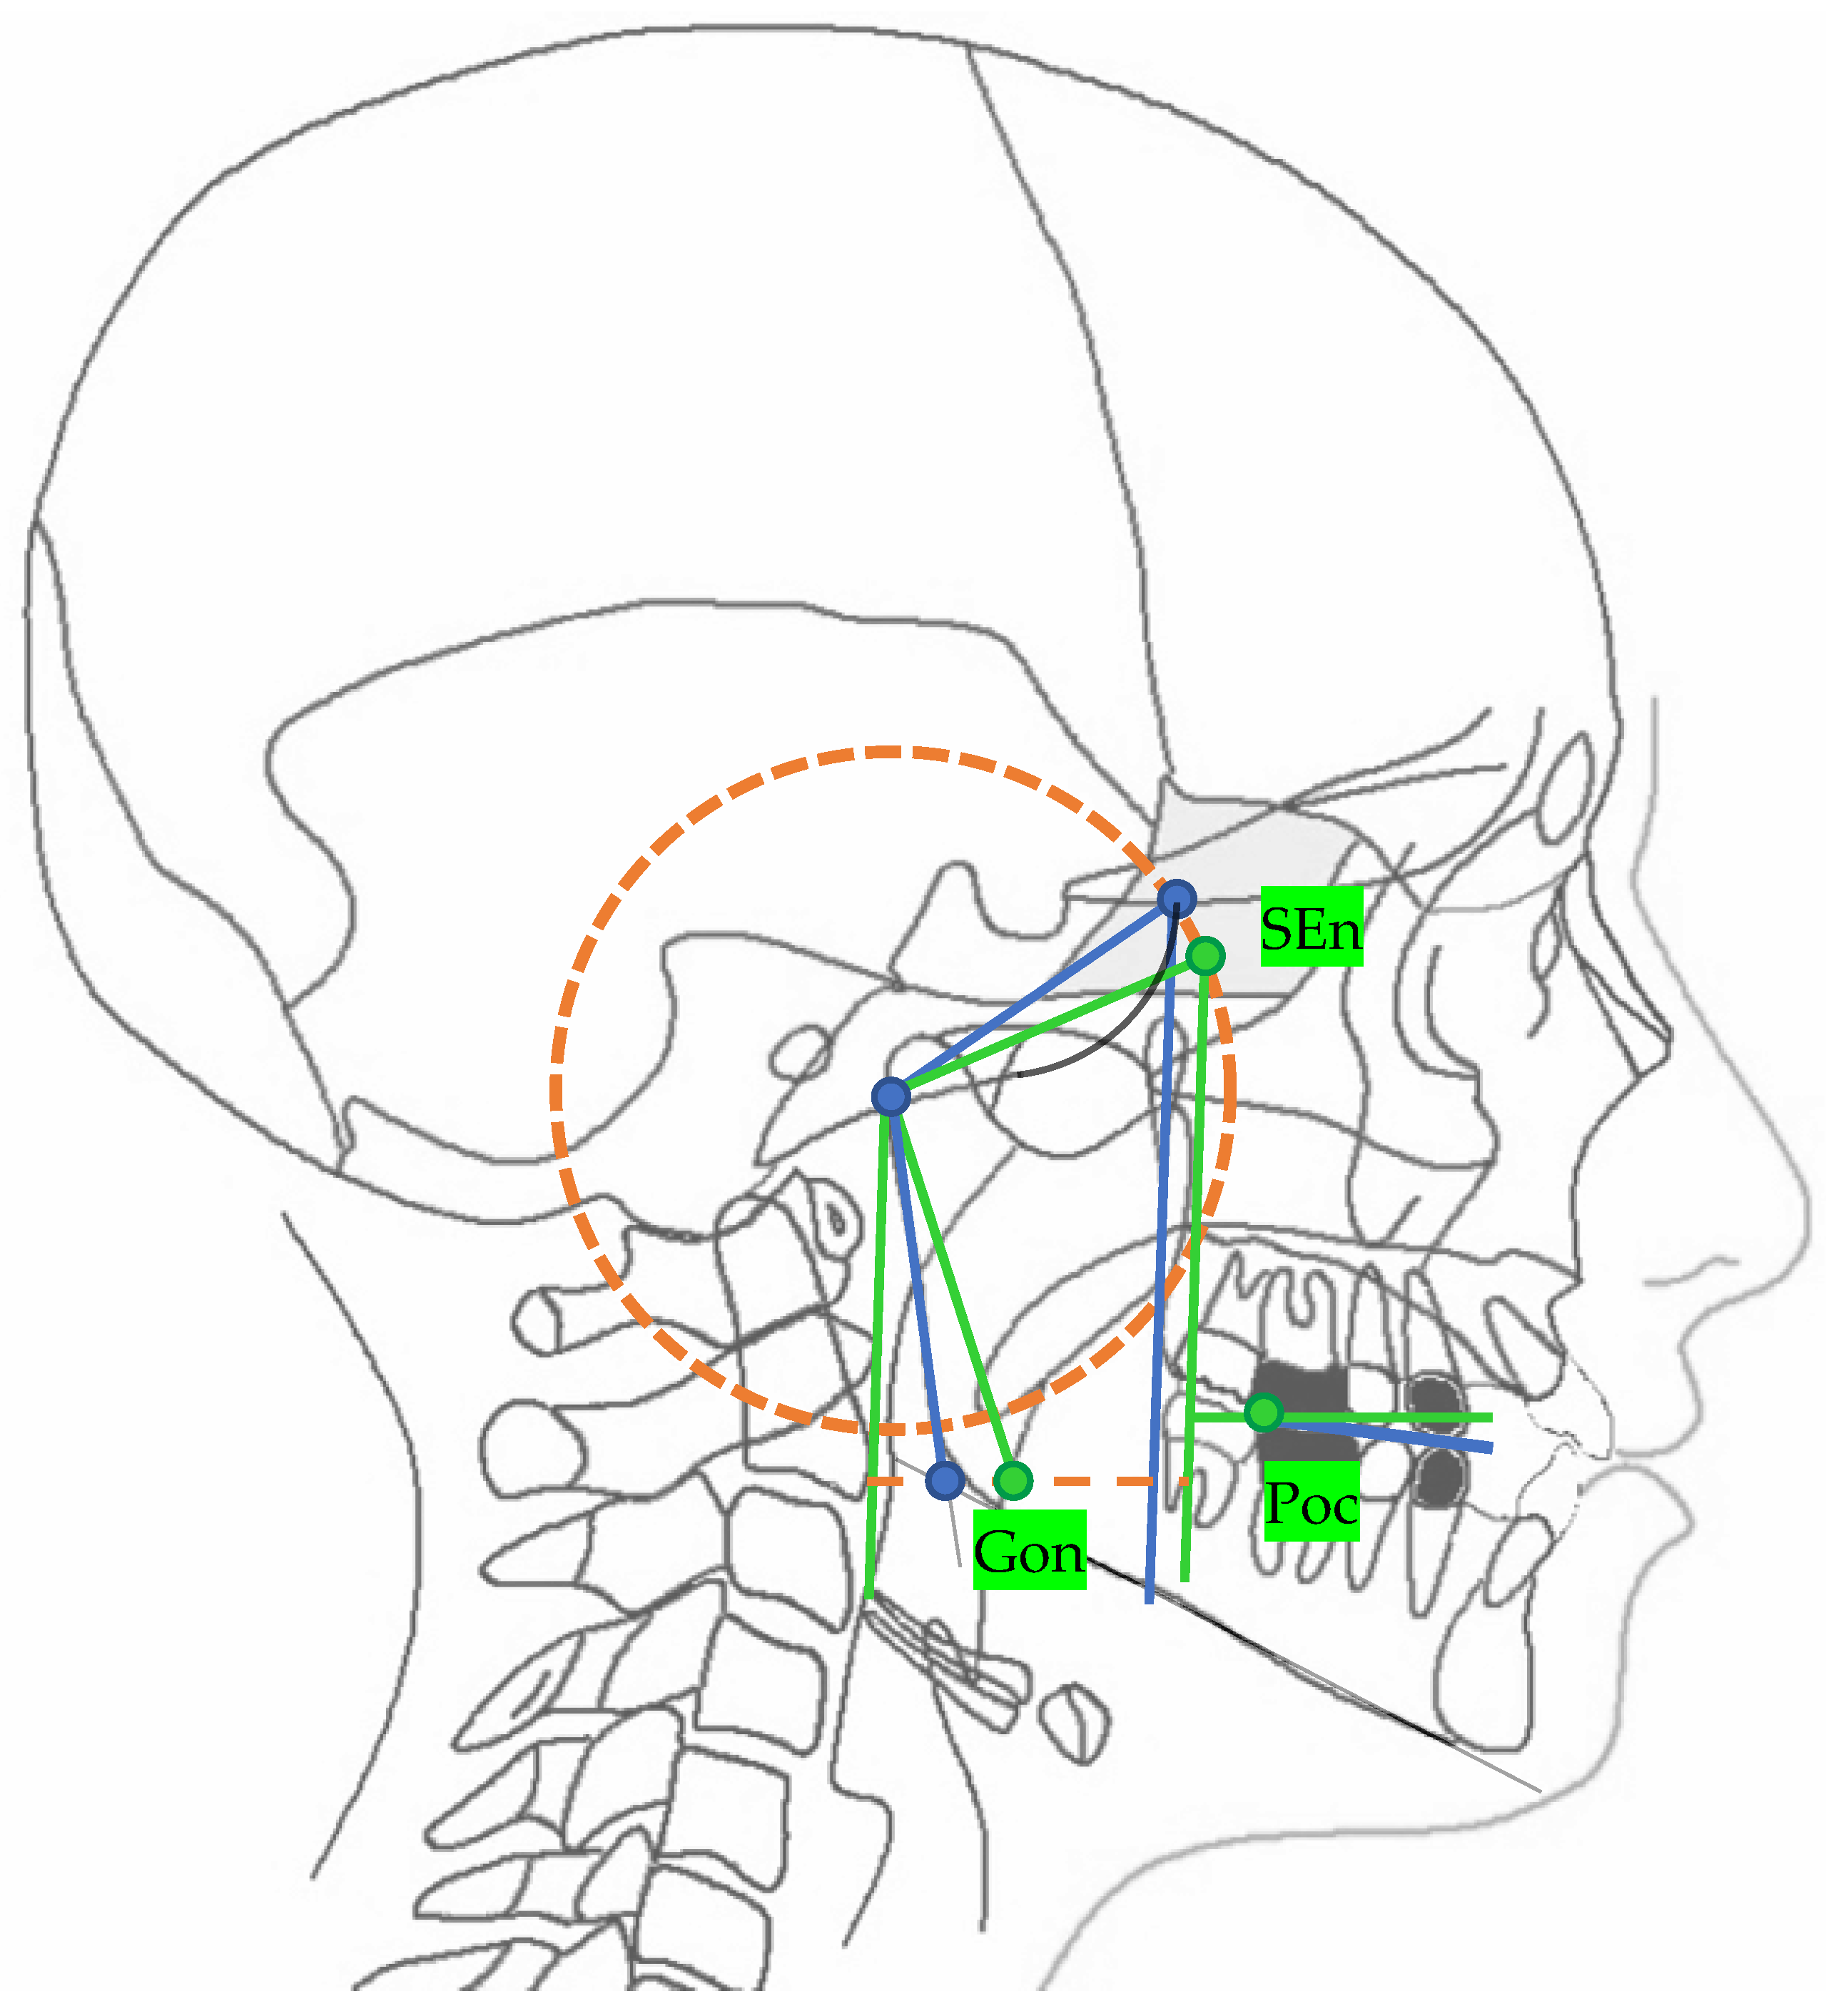

| Landmarks | |

|---|---|

| SE | Sphenoethmoidal junction: the intersection of the averaged image of the right and left shadows of the great wings of the sphenoid with the floor of the anterior cranial fossae |

| Ar | Articulare: the point of intersection between the posterior margin of the ramus and the outer margin of the cranial base |

| Ptm | Pterygomaxillary fissure: the lowest point in the contour of the pterygomaxillary fissure formed anteriorly by the retromolar tuberosity of the maxilla and posteriorly by the anterior curve of the pterygoid process of the sphenoid bone |

| Go | Gonion: the geometric construction point given by the intersection of two lines wherein one passes from Me to the lower most point of the mandibular corpus and the other passes from Ar to the posterior most point of mandibular ramus |

| Poc | Posterior occlusal contact: the most supero-distal contact point of the first molars |

| Aoc | Anterior occlusal contact: the most mesial contact point of the first premolars or first deciduous molars |

| Lines | |

| MCF | Middle Cranial Floor, SE—Ar |

| PM | Pterygo-Mandibular plane, SE—Ptm |

| MR | Mandibular Ramus, Ar—Go |

| FOP | Functional Occlusal Plane, Poc—Aoc |

| SEn | SE neutral: the point of a circumference with the center in Ar and the radius equal to the MCF, in which an angle of the skull base equal to 40.3° is obtained |

| Gon | Gonion neutral: the point located at the same level of the Go and halfway between the PMn line and its parallel passing through Ar |

| PMn | PM neutral: the line parallel to the PM forming at the point SEn an ideal angle of 40.3° with the MCFn |

| MCFn | MCF neutral, Ar—Sen |

| MRn | MR neutral, Ar—Gon |

| FOPn | FOP neutral, plane perpendicular to the PMn passing through Poc |